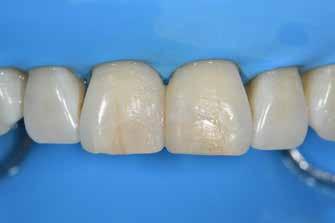

Nem volt kedvencem, de kevésbé kedveltem a hibrid technikát, ahol a palatális fal wax-uppal történő felépítése, majd a nyaki terület szabadkézi megerősítése után a restauráció többi részét mátrixszal lehetett kivitelezni (1. ábra). Bár a kezemben ez valahogy hatékony volt, mégis bonyolult volt.

1. ábra: A wax-up alapú technikák gyakori problémái, a szájpadlásfal apikális része hibás.

2-4. ábra: Gyakori problémák klasszikus megközelítéssel. 5. ábra: Tökéletes vészhelyzeti profil elülső szárnyas technikával. Dr. Jun Iwata, Japán jóvoltából.